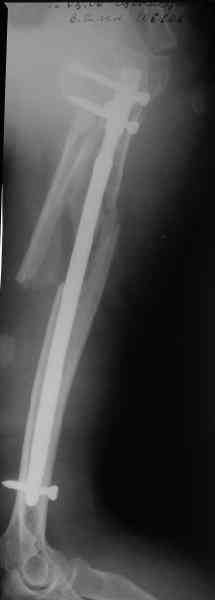

Здесь нет необходимости в серкляже. Вмешиваться на промежуточных отломках приходится, если есть угроза перфорации кожи, или промежуточный отломок попал в фасцию, как пуговица в петлю. В приложении сегментарный оскольчатый перелом плеча в проксимальном отделе, фиксированный больщеберцовым стержнем. Как видите, обошлось без серкляжа. Функция полная.

Это укороченный большеберцовый стержень, которые делает предприятие "ЦИТО".

Доступные на тот момент гвозди для плеча имели худшие возможности фиксации в коротком проксимальном отломке.